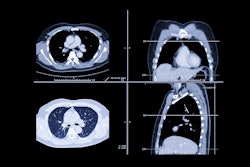

Idiopathic pulmonary fibrosis is a common interstitial pneumonia and has a high mortality rate. That's why being able to accurately assess the disease is key to effective patient management, Nam told attendees. CT plays an important role in the diagnosis of this condition and treatment assessment, but the degree of fibrosis isn't easily quantified on these exams, Nam explained.

Nam's group explored whether adding a deep-learning software to CT imaging could boost the modality's ability to quantify lung fibrosis in patients with the condition via a study that included 161 patients with diagnosed idiopathic pulmonary fibrosis who underwent noncontrast chest CT and spirometry between 2005 and 2009 within three months after receiving their diagnosis. The team used a commercially available deep-learning software (Aview by Coreline Soft) to determine proportions of normal lung volume (CT-Norm%) and fibrotic lung volume (CT-Fib%); they then correlated these results with spirometry results and calculated adjusted hazard ratios of CT-Norm% and CT-Fib%.

The researchers found that the combination of deep learning and CT imaging results showed that both CT-Norm% and CT-Fib% -- when adjusted for age, sex, smoking status, comorbidities of chronic diseases, and the spirometry measures of forced vital capacity (FVC), and diffusing capacity for carbon monoxide (DLCO) -- were predictors of patient survival.

"Normal lung and fibrotic lung volume proportions using a chest CT-based deep-learning algorithm ... correlated with physiologic variables and were independent predictors for overall survival in idiopathic pulmonary fibrosis," Nam concluded.